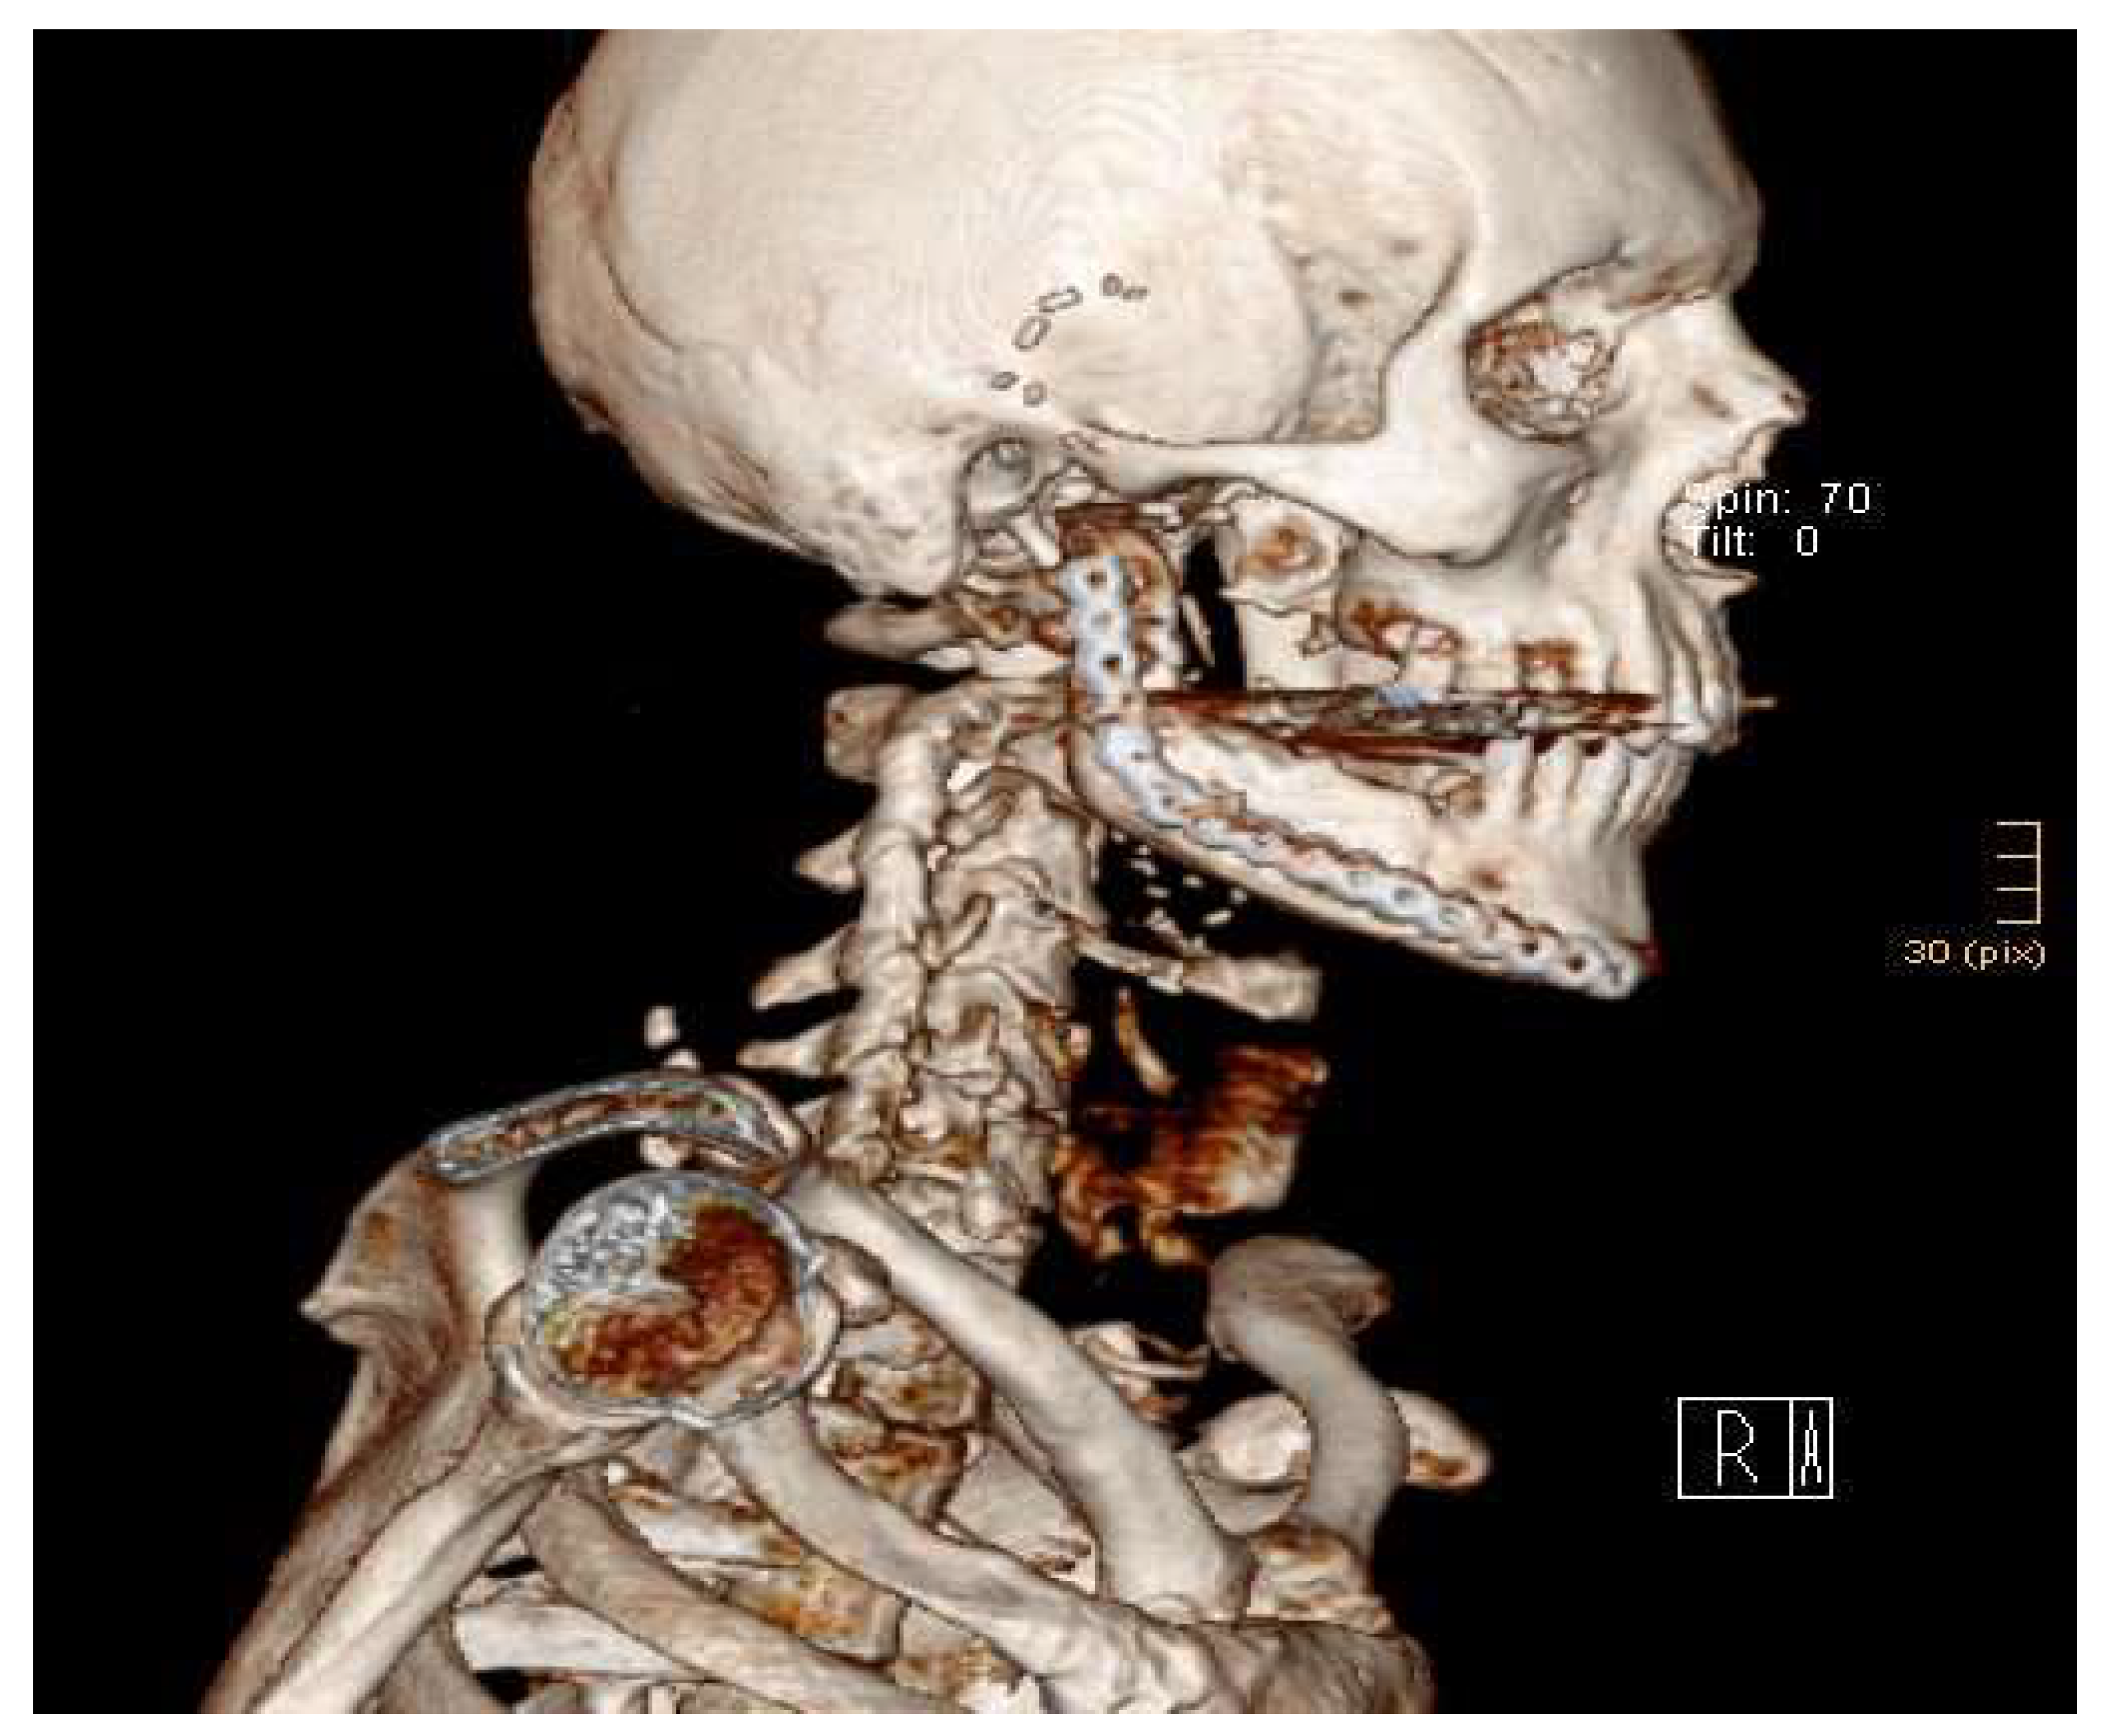

2.2. Surgical Procedure

3. Results

| Patient 1 | 59 | f | Therapy-refractory osteomyelitis | 80 | No | 9 | (Hypo)pigmentation 3, relief 4, all others 0 | Nearly no complaint | 5 mm | 40 mm | 52 | No |

| Patient 2 | 63 | m | Extended recurrent odontogenic keratozyst | 80 | No | 10 | Pliability 1, all others 0 | No complaint | 40 mm | 40 mm | 50 | No |

| Patient 3 | 17 | f | Goldenhar syndrome | 80 | Rarely light pain | Cannot be assessed | Not applicable due to skin transfer | Cannot be assessed | 20 mm | 35 mm | 70 | Yes |

| Patient 4 | 51 | m | Adenocarcinoma of the parotid gland | 80 | Joint noise, no pain | 8 | Not applicable due to skin transfer | Nearly no complaint | 40 mm | 35 mm | 24 | Yes |